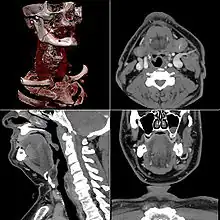

Neck

Contrast CT is generally the initial study of choice for neck masses in adults.[39] CT of the thyroid plays an important role in the evaluation of thyroid cancer.[40] CT scan often incidentally finds thyroid abnormalities, and so is often the preferred investigation modality for thyroid abnormalities.[40]